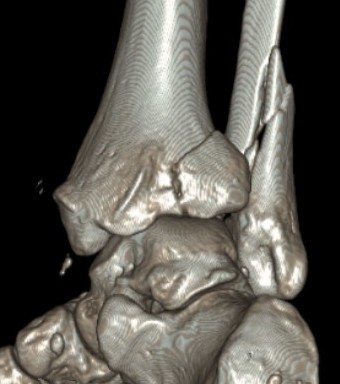

Dislocated ankle joint with large posterior malleolus

Articular incongruency

Posterior malleolus and syndesmotic injury